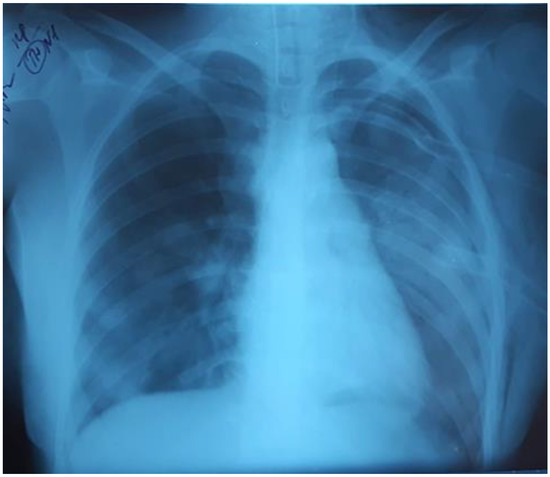

The child’s condition deteriorated within three days. The RF progressed; RR 35/min, SpO286%, oxygen dependence, HR 110/min, BP 100/60 mmHg, the symptom of capillary refill > 3 s, cold extremities. Bilateral polysegmental pneumonia was detected on the chest radiograph (Figure 3). The lung ultrasound showed signs of interstitial syndrome on both sides, alveolar consolidation on the left, left-sided hydrothorax.

Figure 3.

Bilateral polysegmental pneumonia.